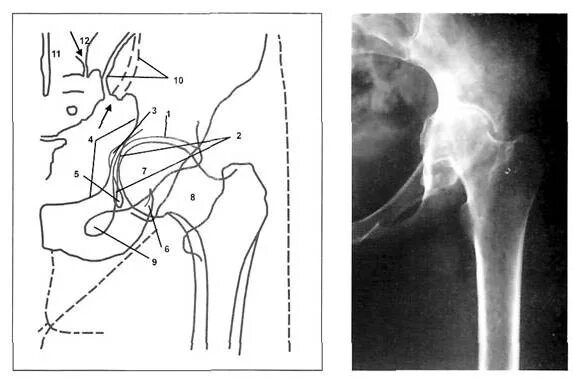

Рентген тазобедренный в двух проекциях